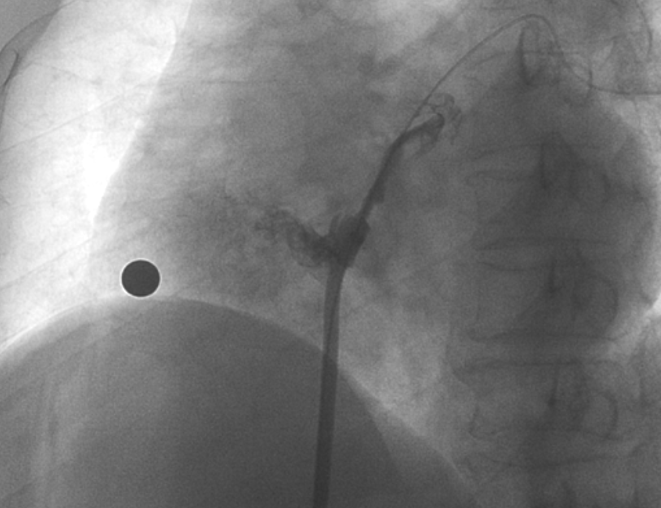

術(shù)中造影顯示患者為PFO且長隧道型,目前市場上已商業(yè)化的PFO封堵器難以滿足該患者解剖結(jié)構(gòu)封堵需求。迪創(chuàng)醫(yī)療自主研發(fā)的OmniSeal PFO封堵器自適應(yīng)性雙盤貼合設(shè)計能廣泛適應(yīng)不同PFO隧道長度的解剖結(jié)構(gòu)和形態(tài),其雙盤外包覆式阻流和隧道內(nèi)填充阻流相結(jié)合的雙重阻流設(shè)計,可為此患者實現(xiàn)有效封堵。與此同時,OmniSeal首創(chuàng)的完全可穿刺式設(shè)計,也為此患者最大程度地保留了房間隔區(qū)域穿刺通道,以實現(xiàn)全兼容未來可能的左心系統(tǒng)二次介入術(shù)。術(shù)終造影和心臟超聲顯示封堵完全、效果良好。作為OmniSeal的首例臨床應(yīng)用,本次手術(shù)的順利完成和優(yōu)異效果充分體現(xiàn)了產(chǎn)品的設(shè)計創(chuàng)新優(yōu)勢。

造影顯示PFO封堵完全,無殘余分流, 試驗器械充分舒展并貼合良好